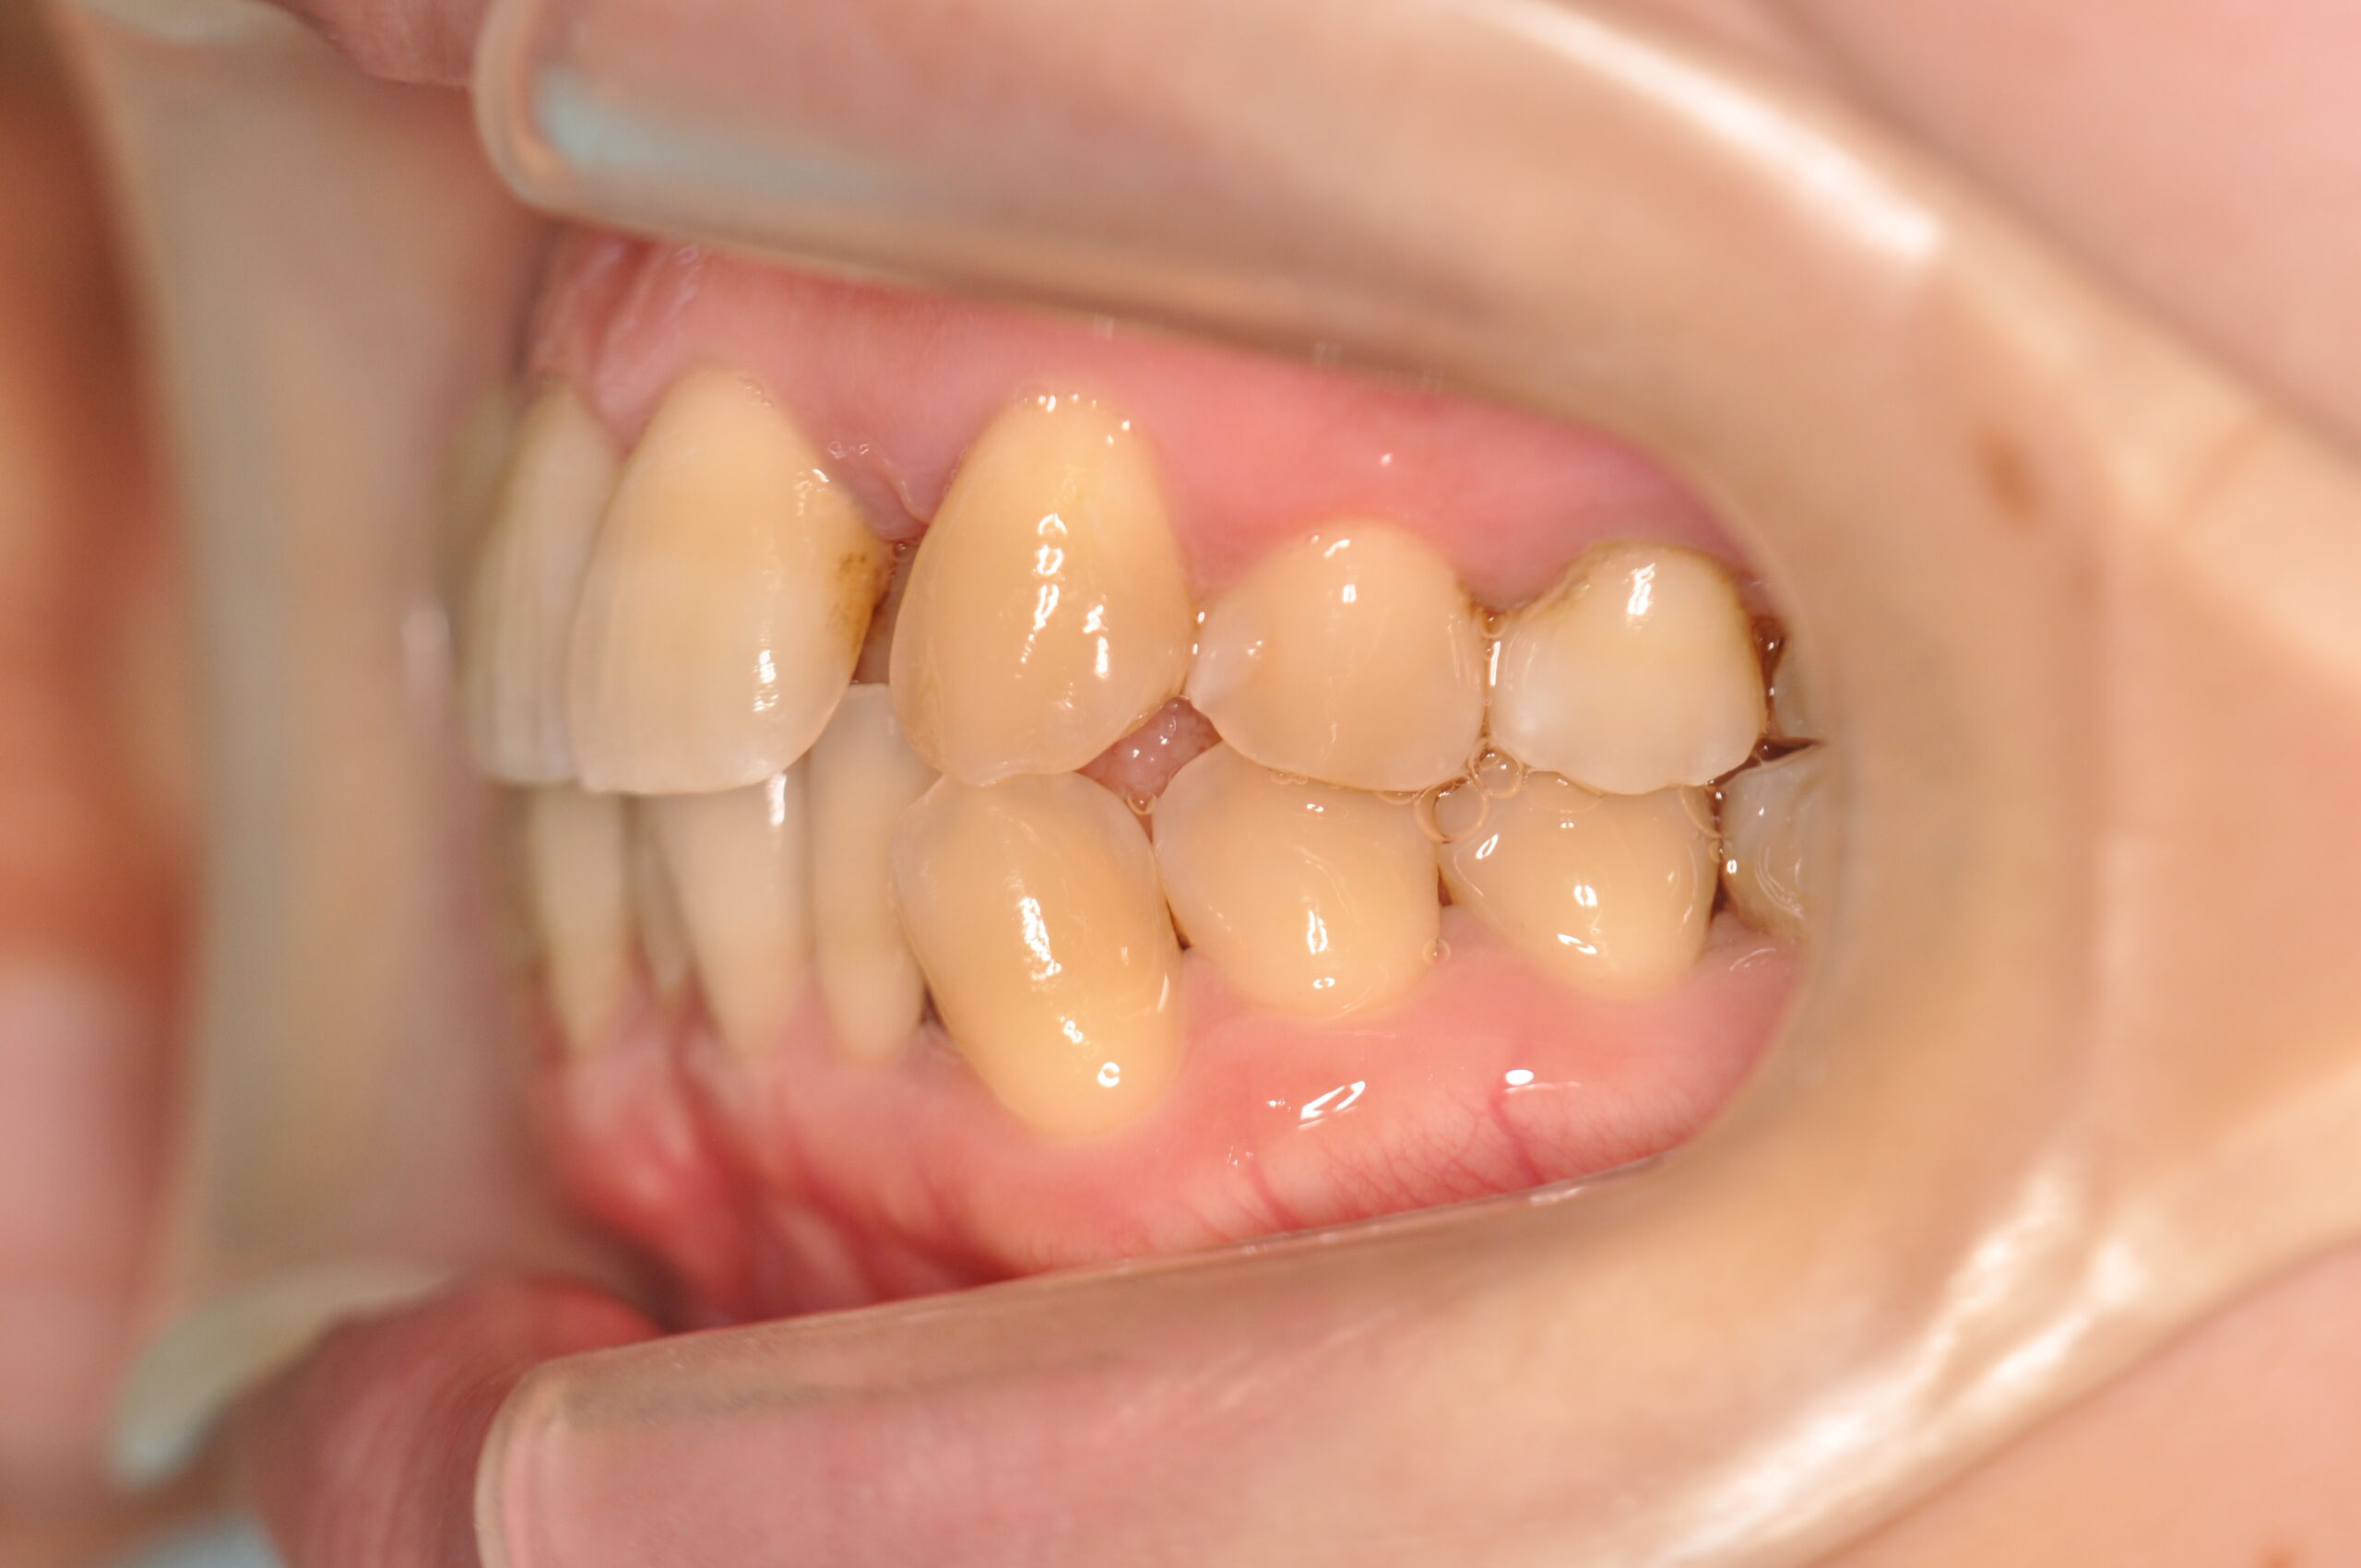

| 治療内容の詳細 | 初診時31歳の女性で、前歯が奥側にあることを気にされ来院されました。 検査の結果、上下顎叢生を伴うアングルⅠ級不正咬合と診断しました。 治療としては、上顎臼歯部の遠心移動を行い、歯を配列するためのスペースを確保し、非抜歯の上、セルフライゲーションブラケット装置(デーモンシステム)で歯の配列と咬合関係の改善をを行いました。 治療期間は、2年7ヶ月でした。 |